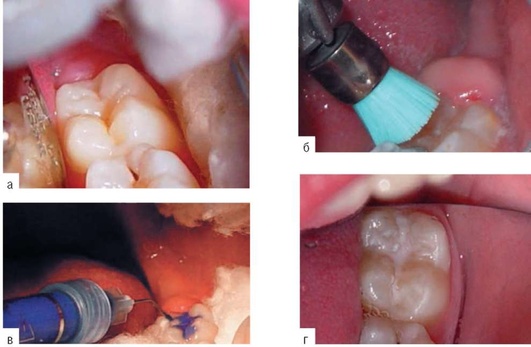

Методика проведения (рис. 22-3)

-

Очищают зуб с помощью механической щетки и полировочной пасты. Более эффективную очистку жевательной поверхности осуществляют с помощью пескоструйных аппаратов с бикарбонатом натрия («Air Flow», «Hand Blaster»).

-

Изолируют зуб от ротовой полости и протравливают 30-37% раствором либо жидкотекучим гелем низкой вязкости фосфорной кислоты в течение 60 с.

-

Удаляют протравочный агент с помощью струи воды в течение 40-60 с. Высушивают зуб.

-

Вносят герметик с помощью зонда, канюли. Материал тщательно распределяют во избежание образования пор. Герметик помещают только в ямки и фиссуры, нельзя покрывать материалом скаты бугров. Избыточное нанесение материала нарушает окклюзию. При этом кусочки герметика скалываются, а по краям отломов создаются новые ретенционные участки для скопления бактериального зубного налета. У детей верхние первые постоянные моляры нередко прорезываются с добавочными небными буграми, фиссуры, окаймляющие небный бугор, также подлежат герметизации. Кроме того, герметизации подлежат и щечные ямки прорезывающихся нижних первых постоянных моляров, и небные ямки верхних резцов.

-

Удаляют излишки, контролируют окклюзию. При технологии нанесения герметика в два слоя неизбежны излишки первого ненаполненного композита на пришеечных и апроксимальных участках зуба, так как распределение первого слоя происходит воздушной струей. Удаляют излишки скалером, зубным флоссом. При правильном нанесении герметика контроля окклюзии не требуется; если необходима коррекция герметика, используют алмазные боры, финиры и полиры.